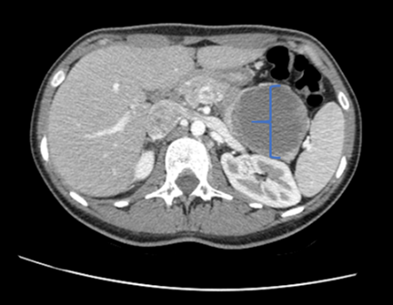

Figure 1: This axial contrast-enhanced abdominal CT shows a well-circumscribed mass located in the tail of the pancreas.